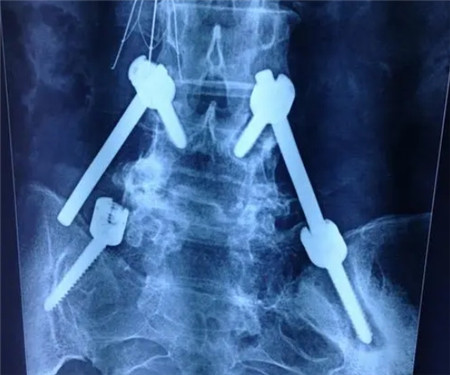

X线片、CT或MRI提示腰椎骨折影像学改变。

1.X线摄片

正位和侧位平片是最基本的检查方法,可评估椎体高度丢失情况、骨折线位置、椎体顺列变化、腰椎后凸畸形程度等。